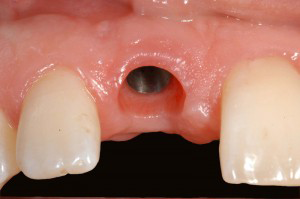

Behandlingen innebærer at man opererer en liten skrue i titan inn i kjevebenet. Denne erstatter roten som mangler. På implantatet festes siden en krone eller en bro.

Grunnstoffet titan(Ti) aksepteres av kroppen nesten som om det var dens eget vev, og dette gjør at pasienten kan få nye røtter fremstilt i titan. Med en liten operasjon vil tannlegen feste titanskruer, eller implantater som er fagbetegnelsen, i kjeven. Disse titanimplantatene vokser fast i kjevebenet. På implantatet festes siden en liten mellomdel kalt distanse, som stikker så vidt gjennom tannkjøttet. En krone eller bro skrues deretter fast på distansen.

- mangler èn tann. Man opererer inn et implantat og fester en krone på implantatet. Dette anbefales særlig der nabotenner er feilfrie eller har små fyllinger.